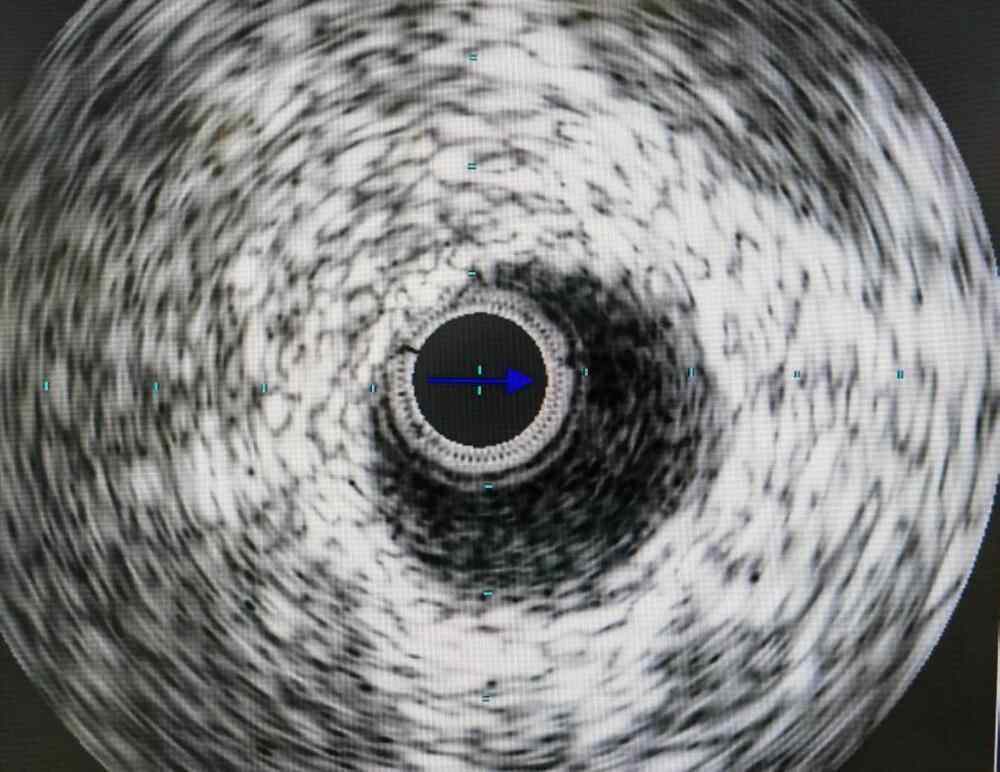

历时1小时15分钟,导丝终于成功穿过患者闭塞段。为确保支架植入精准,黄火剑启用冠脉血管内超声(IVUS),如同给血管做“高清CT”,清晰显示斑块性质与血管夹层风险。在IVUS引导下,支架被稳稳植入闭塞段,随着球囊扩张“嘭”的一声,造影剂顺利流过原本闭塞的血管——被阻断的“生命通道”成功打通!